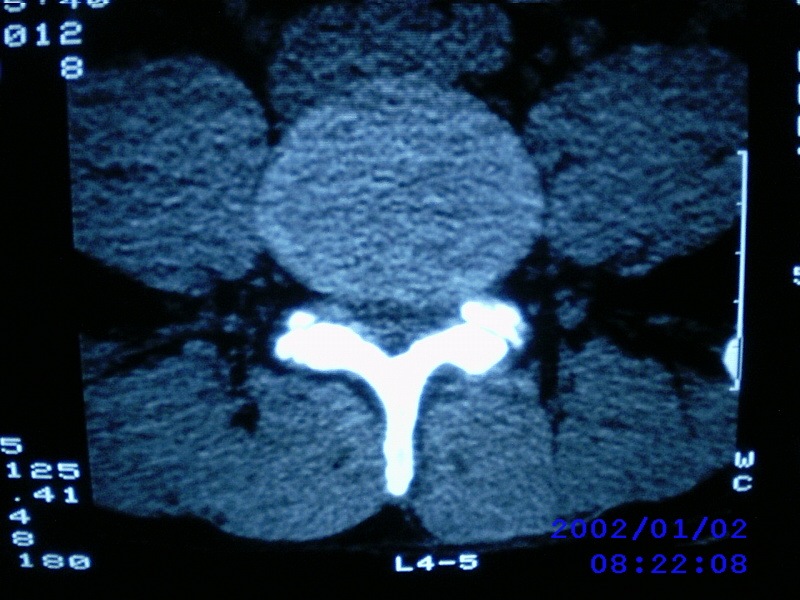

患者,男性,40岁,腰痛伴左下肢疼痛、麻木6年。5年前做过腰椎间盘手术,具体是哪个位置病人记不清了。

我拍的是l4-5、l5-s1

1)l4/5及l5/s1左侧椎板术后改变。2)l5/s1椎间盘突出,l5椎体下缘许莫氏结节。3)l4/5椎间盘膨出并突出。4)l3/4椎间盘膨出。

l4/5及l5/s1左侧椎板术后改变